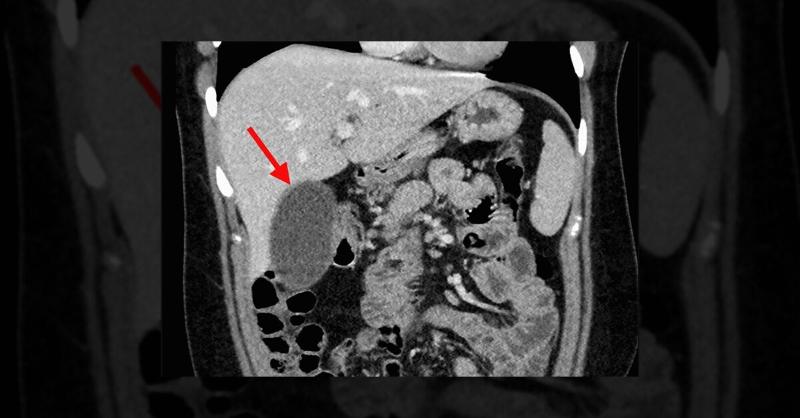

A 21-year-old woman presented with escalating pain in the right upper quadrant and epigastric region, radiating to her back. She experienced stabbing, and cramping pain along with nonbloody, nonbilious vomiting, worsening over seven days. Similar symptoms had appeared during her pregnancies in the past. Previously, she underwent common bile duct st